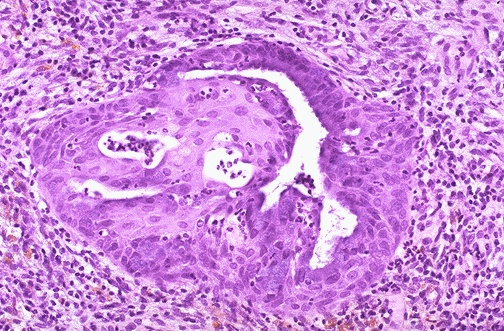

Image 7.4

The appearance of an endocervical gland is shown here. What type of epithelium is present?